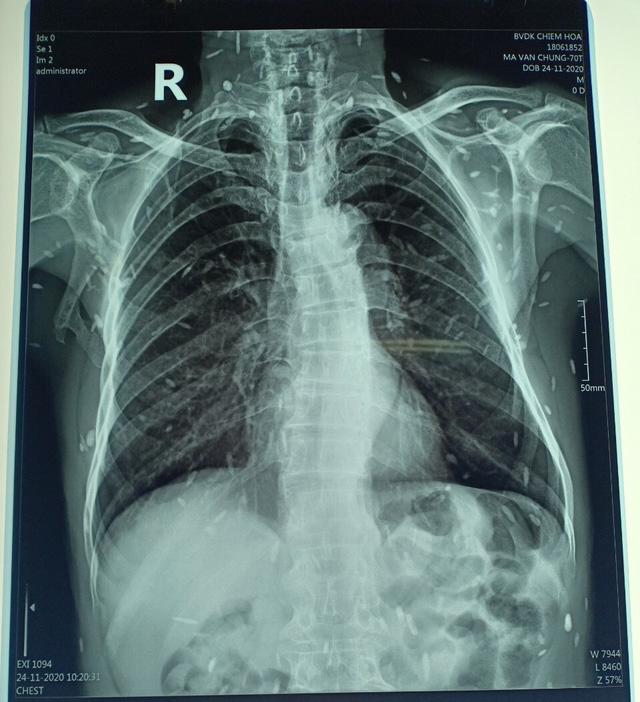

Hình ảnh chụp X-quang nam bệnh nhân 70 tuổi mắc bệnh kén sán toàn thân. Ảnh: TTYT huyện Chiêm Hoá

BS.ThS Phạm Chí Cường cho biết: "Cụ ông nhập viện vì đau răng, nhai kém và khó há miệng. Khi chụp X-quang thì kết quả là viêm quanh cuống răng. Thế nhưng, hình ảnh chụp thì cho ra rất nhiều sán, kén sán, các ổ vôi hoá nhu mô não do sán".

Đến nay, dù qua nhiều ngày điều trị tích cực nhưng số lượng sán thấy được qua hình ảnh chụp X-quang không thể xử lý hết trong ngày một ngày hai nên khi kết quả điều trị tích cực, chúng tôi đã cho bệnh nhân xuất hiện và điều trị theo các đợt thuốc. Sau đó, cho bệnh nhân đến kiểm tra, theo dõi thường xuyên", BS.ThS Phạm Chí Cường cho hay.